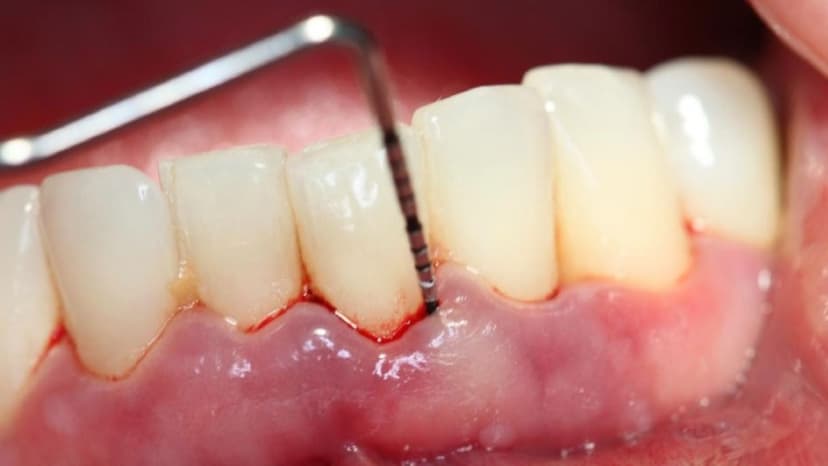

Viêm nướu là tình trạng viêm nhiễm của nướu, gây ra các triệu chứng như sưng đỏ, chảy máu chân răng, hơi thở có mùi hôi, v.v. Đây là bệnh lý rất dễ xảy ra. Đồng thời, khi không được điều trị kịp thời, người bị viêm nướu có thể phải đối diện với những biến chứng nguy hiểm như viêm nha chu, ảnh hưởng đến sức khỏe răng miệng và toàn thân.

1.2. Dấu hiệu nhận biết

Viêm nướu không quá khó nhận biết vì các triệu chứng lâm sàng của bệnh khá rõ ràng:

– Nướu sưng đỏ

– Tình trạng chảy máu chân răng, thường dễ nhận thấy nhất khi khi đánh răng hoặc dùng chỉ nha khoa

– Hơi thở có mùi hôi

– Nướu mềm

– Răng lung lay

– Đau nhức, ê buốt

– Nướu tụt, lộ chân răng